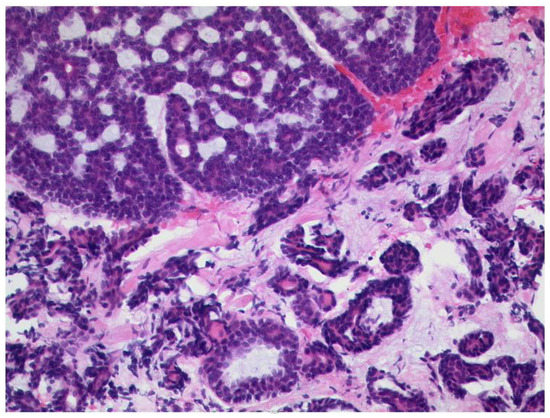

3.3.3. Tumors of the Lacrimal Gland

- Andreasen, S.; Esmaeli, B.; Holstein, S.L.; Mikkelsen, L.H.; Rasmussen, P.K.; Heegaard, S. An Update on Tumors of the Lacrimal Gland. Asia Pac. J. Ophthalmol. 2017, 6, 159–172. [Google Scholar] [CrossRef]

- Young, S.M.; Kim, Y.D.; Shin, H.J.; Imagawa, Y.; Lang, S.S.; Woo, K.I. Lacrimal gland pleomorphic adenoma and malignant epithelial tumours: Clinical and imaging differences. Br. J. Ophthalmol. 2019, 103, 264–268. [Google Scholar] [CrossRef] [PubMed]

- Qin, W.; Chong, R.; Huang, X.; Liu, M.; Yin, Z.Q. Adenoid cystic carcinoma of the lacrimal gland: CT and MRI findings. Eur. J. Ophthalmol. 2012, 22, 316–319. [Google Scholar] [CrossRef] [PubMed]

- Gao, Y.; Moonis, G.; Cunnane, M.E.; Eisenberg, R.L. Lacrimal gland masses. AJR Am. J. Roentgenol. 2013, 201, W371–W381. [Google Scholar] [CrossRef]